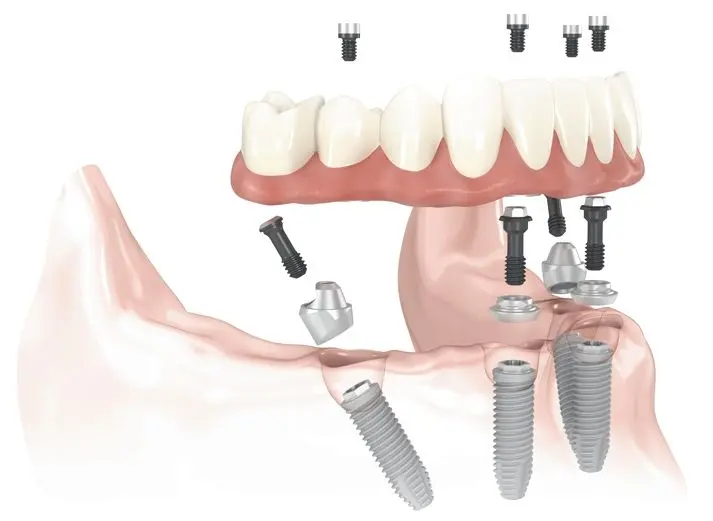

Kako deluje All-On-4?

Drugi korak naprej glede na mobilne proteze je danes zelo priljubljena metoda All-On-4. S to metodo izdelamo zobni nadomestek (zobni most) v spodnji ali zgornji čeljusti (po možnostih tudi obeh, ki je pritrjen na štiri zobne vsadke. All-on-4 je priljubljen tudi zato, ker je to najcenejša fiksna rešitev za brezzobo čeljust.

Pred posegom je na vrsti podrobna diagnostika, možna ekstrakcija preostalih zob in možna okrepitev čeljusti po metodi vgradnje umetne kosti. V enem dnevu, torej v enem obisku, vam v čeljust vgradimo 4 zobne vsadke. Namestitev enega vsadka traja približno 15 minut, kar pomeni, da bo vaš prvi obisk, torej celoten poseg, ki vključuje tudi morebitno ekstrakcijo zoba, vgradnjo 4 vsadkov, anestezijo in pogovor z zdravnikom, trajal približno 2 uri. Sprednja 2 vsadka se namestita pravokotno na čeljust, zadnja dva pa pod kotom od 35 do največ 45 stopinj. Ta posebna tehnika implantacije omogoča vgradnjo vsadkov tudi ljudem, ki nimajo dovolj volumna kosti za klasičen vsadek.

Kaj je All-On-6?

Kot najboljša rešitev za brezzobo čeljust v primeru dobrega volumna in strukture kosti vam bomo priporočili možnost fiksnega zobnega mostu na 6 vsadkih. Lahko bi rekli, da je ta metoda funkcionalno in estetsko najnaprednejša različica fiksnega protetičnega dela na vsadkih. Prav tako v celoti zadovolji paciente z visokimi estetskimi zahtevami.

Praviloma je vedno bolje imeti čim več nosilcev za protetično delo. Vendar pa je treba upoštevati, da je zaradi majhne količine ali slabe kakovosti kosti pri nekaterih pacientih omejeno število vsadkov, ki jih je mogoče vsaditi.